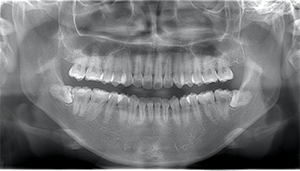

左下の歯茎が腫れている親知らずの症例

左下の親知らず周囲歯肉が腫れていました。

また、手前の歯との間で虫歯もできていました。

| 抜歯内容 | 下顎の親知らずの抜歯希望の患者様です。 智歯周囲炎となっており、初診時では麻酔が効きづらい旨をお話しし、初診時は抗生物質をお出ししました。1週間後、ある程度歯肉の炎症がとれたことを確認して抜歯を行いました。 麻酔を行い、遠心(親知らずの奥側)歯肉と、手前の歯の頬側の歯肉を切開しました。 歯茎を開いて、手前の歯と引っかかっている部分をカットしました。 その後、骨からでている歯冠部(頭の部分)をカットしました。 その後へーベルで歯根(骨に埋まっている部分)を脱臼し、抜歯を終えました。 切開した歯茎を3針縫って、治療終了となりました。 歯茎を切ったため、3日ほど腫れぼったい感じがあったようですが、痛みはほとんどなく、治癒に向かいました。 |